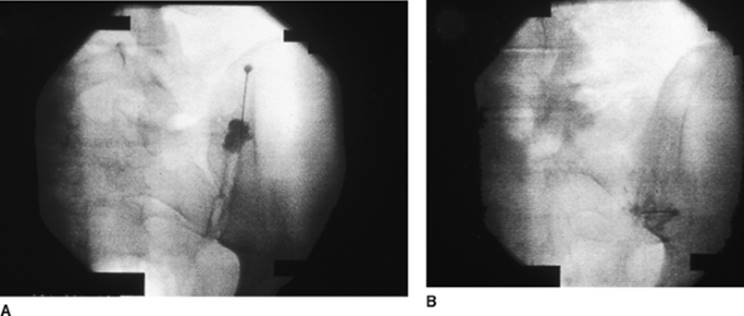

Approach and Technique: After sterile preparation of the region, the sacroiliac joint is identified under fluoroscopy in the anteroposterior view (Fig. 70-1A). To gain access to this joint space, the fluoroscopic beam must be rotated approximately 15° to 30° to the opposite side of the joint to locate the posterior face of the sacroiliac joint, and then 20° to 30° cephalad and caudad (Ferguson view; Fig. 70-1B). Two separate injections can be performed. The first injection is aimed at the inferior one-third of the joint. Accordingly, the 22-gauge spinal needle is aimed in the same direction as the fluoroscopic beam to gain access to the joint. A loss of resistance is often felt as the joint space is entered. Next, the superior one-third of the joint space is entered in a similar fashion. To help confirm the joint space location, 0.5 to 1.0 mL of contrast dye can be injected prior to the injection of the local anesthetic mixture.

Figure 70-1. A: Anteroposterior view. B: Ferguson view.